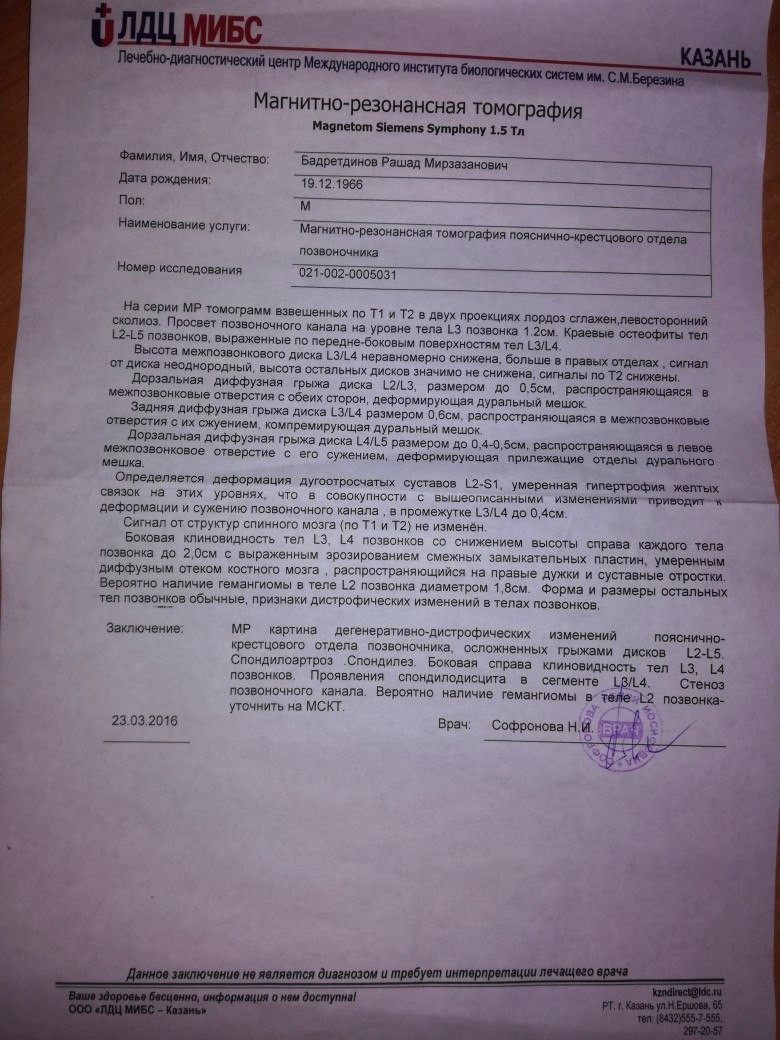

Мрт картина дегенеративно дистрофических изменений пояснично крестцового отдела позвоночника